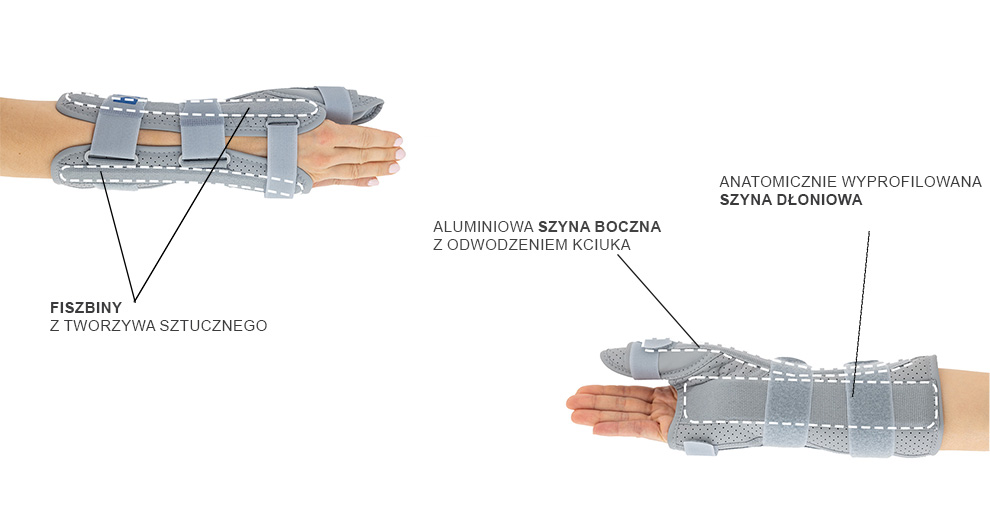

OTWARTA ORTEZA RĘKI I PRZEDRAMIENIA ZE STABILIZACJĄ KCIUKA

Otwarta orteza nadgarstka została wykonana według nowego bardziej anatomicznego kształtu, dzięki czemu lepiej stabilizuje staw promieniowo-nadgarstkowy i nadgarstek. Wyrób posiada konstrukcję otwartą, co ułatwia jego zakładanie na kończynę oraz regulowane zapięcie przednie, co czyni ortezę jeszcze bardziej uniwersalną i ułatwia dopasowanie do każdego kształtu dłoni. W górnej części wyrobu zainstalowano dwie fiszbiny ortopedyczne, które wraz z łyżką dłoniową przekrojowo tworzą trzy obwodowe punkty podparcia kończyny górnej. Taki sposób stabilizacji przedramienia jest sposobem najbardziej skutecznym. Zapięcia wyrobu wykonano przy użyciu zespołu dwóch szerokich taśm obwodowych oraz jednej wąskiej taśmy dłoniowej. Zakres regulacji zapięć jest bardzo duży i dzięki temu gwarantuje on szeroki zakres regulacji i stabilizacji. Orteza została w całości wykonana z nowego innowacyjnego surowca AirSanmed II™. W dłoniowej części ortezy zainstalowano miękką elastyczną poduszkę poprawiającą komfort użytkowania wyrobu. Konstrukcja ortezy oraz użyte surowce przeciwdziałają wystąpieniu u jej użytkowników zespołu cieśni nadgarstka. W wyrobie zamontowano taśmę stabilizującą kciuk, której nadmiar po dopasowaniu należy odciąć. Dodatkowo w wyrobie zainstalowano aluminiową szynę boczną ze stabilizatorem, której zadaniem jest funkcja odwiedzenia kciuka. Zakres i sposób jego odwiedzenia może być dowolnie kształtowany przez odpowiednie przegięcie szyny. Stabilizacja 3 punktowa

Usztywnienia

Łyżki nadgarstków

Łyżki nadgarstkowe, to specjalnie ukształtowane usztywnienie odzwierciedlające ukształtowanie tej części ciała od spodu. Posiadają one wsparcie śródręcza oraz przedramienia. Wykonane są ze specjalnie usztywnionego aluminium oraz w zależności od przeznaczenia posiadają różne rozmiary, różne kształty, różną szerokość i grubość. Ich końce są mocno zaokrąglone co skutecznie zabobiega przebiciu tunela w którym zostały zamontowane.

Usztywnienie kciuka

Usztywnienia kciuka stosowane są do produkcji niektórych typów ortez nadgarstka, zostały wykonane ze stali, wyoblone, wstępnie wyprofilowane anatomicznie i wyposażone w ażurowy stabilizator kciuka. Usztywnienia montowane są w elementy miękkie ortez nadgarstka do specjalne w specjalnie do tego przygotowane kanały. W celu zabezpieczenia usztywnień przed szkodliwym działaniem potu i wody, zostały one ocynkowane. Bardzo ważną kwestią jest fakt, aby usztywnienia kciuka zostały tylko uformowane wstępnie, w celu umożliwienia przymierzenia pacjentowi ortezy, po właściwym doborze jej rozmiaru, wymagane jest precyzyjne dogięcie stabilizatora, w celu uzyskania pożądanego przez lekarza lub terapeutę ustawienia kciuka pacjenta.

Fiszbiny plastikowe

Fiszbiny plastikowe występują w różnych szerokościach i grubościach, wykonane są z różnego rodzaju tworzyw sztucznych, takich jak poliamid, ABS czy akryl, a cechy te decydują o ich sztywności. Dzięki takiej konstrukcji są odporne na wodę, wilgoć i pot. Wyroby wyposażone w nie mogą być prane bez konieczności ich wymontowywania z ortezy. Nasze fiszbiny plastikowe pracują tylko w jednym kierunku doskonale stabilizują bocznie zabezpieczoną część ciała dopasowując się jednocześnie do niego oraz posiadają pamięć, dzięki której zawsze powracają do pierwotnego kształtu. Funkcja ta powoduje, że fiszbiny w ortezie tak samo stabilizują kończynę opuchniętą bezpośrednio po urazie, jak i po zejściu opuchlizny. Nie podlegają one możliwości doginania i korygowania przez to postawy ciała lub zabezpieczonego stawu.